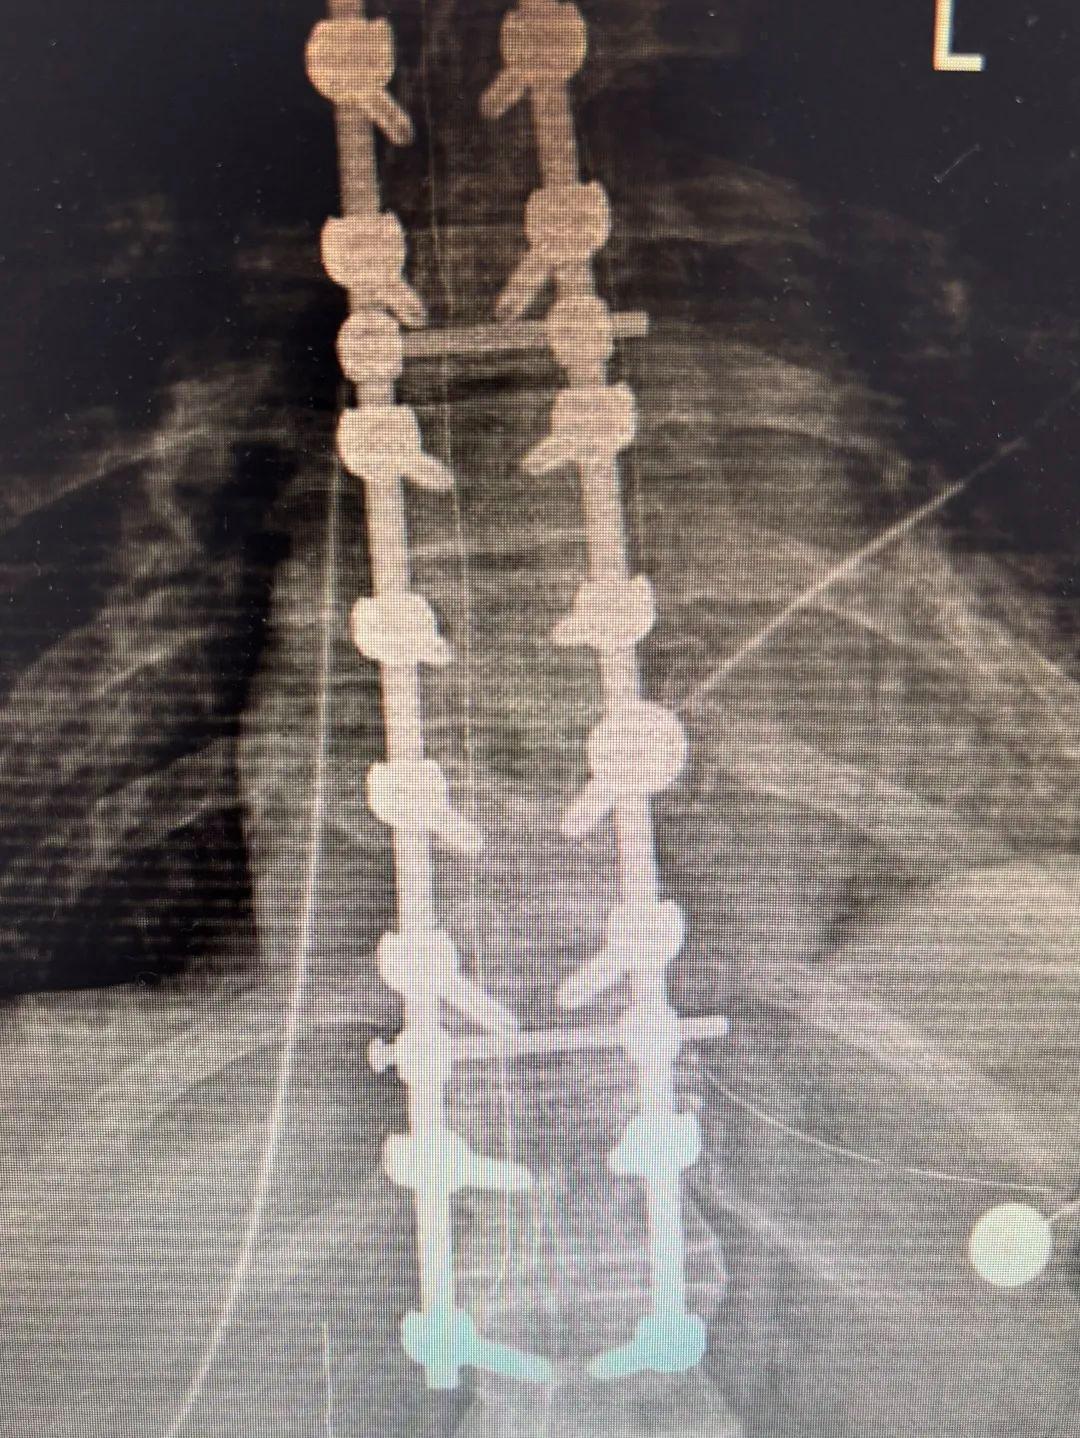

手术前,在脊柱外科耿晓鹏主任大夫、王大巍副主任大夫、刘彬主治大夫与麻醉科、胸外科、神经外科、介入外科等多学科密切合作下,充分评估了患者的术前状态,确保手术粗略在尽可能安全的环境下进行。 术中患者出血约800ml,麻醉及照料团队实时给以输血4U及400ml血浆,使得患者在褂讪的血容量下完成手术。议论患者胸椎脱位重,一次性复位难度极大,术中王大巍大夫创造性地摄取了椎体序贯复位的措施逐渐使患者的胸椎无缺复位。最终经过近5个小时的不懈奋发终于打赢了这场力图的构兵,术后X片走漏内固定位置高超,椎体复位甘心。术后,患者参加急诊重症监护室进行呼吸撑捏调整,并加强抗感染、养分撑捏和抗凝调整等措施。经调整后,患者状态褂讪,已不错指导支具坐立。3月12日,奏凯出院。

术中患者出血约800ml,麻醉及照料团队实时给以输血4U及400ml血浆,使得患者在褂讪的血容量下完成手术。议论患者胸椎脱位重,一次性复位难度极大,术中王大巍大夫创造性地摄取了椎体序贯复位的措施逐渐使患者的胸椎无缺复位。最终经过近5个小时的不懈奋发终于打赢了这场力图的构兵,术后X片走漏内固定位置高超,椎体复位甘心。术后,患者参加急诊重症监护室进行呼吸撑捏调整,并加强抗感染、养分撑捏和抗凝调整等措施。经调整后,患者状态褂讪,已不错指导支具坐立。3月12日,奏凯出院。

胸椎脱位内固定手术的难度与风险滨医附院脊柱外科主任耿晓鹏先容,胸椎脱位内固定手术在脊柱外科中属于高难度手术。率先,与腰椎比较,胸椎脊柱结构的椎弓根细,置钉难度较大,且脱位椎体紧邻降主动脉及肺腔,椎体复位经过中有大出血、损害肺脏等多种可能,存在较高的手术风险。其次,胸椎区域由于其与脊髓的紧密关系,任何失慎的操作齐可能导致脊髓进一步损害或神经功能恶化。临了,由于患者为多发伤,且随同肋骨骨折、胸腔积液等多重伤情,手术操作空间褊狭,骨折复位和内固定的精准度条目极高,迥殊是在出血较多的情况下,术中对出血的收场也成为手术的一大挑战。这次手术的见效,不仅彰显了脊柱外科团队不凡的专科本领与高尚的期间水平,更充分体现了滨医附院在靠近复杂且高风险病例时,所展现出的优质高效的团队融合与搪塞能力。脊柱外科团队凭借致密入微的手术有筹商与全院多学科的紧密配合,共同融合,见效为患者排除了脊柱脱位对脊髓变成的压迫,极地面改善了患者的生活状态与生活质料。举报/响应av番号

胸椎脱位内固定手术的难度与风险滨医附院脊柱外科主任耿晓鹏先容,胸椎脱位内固定手术在脊柱外科中属于高难度手术。率先,与腰椎比较,胸椎脊柱结构的椎弓根细,置钉难度较大,且脱位椎体紧邻降主动脉及肺腔,椎体复位经过中有大出血、损害肺脏等多种可能,存在较高的手术风险。其次,胸椎区域由于其与脊髓的紧密关系,任何失慎的操作齐可能导致脊髓进一步损害或神经功能恶化。临了,由于患者为多发伤,且随同肋骨骨折、胸腔积液等多重伤情,手术操作空间褊狭,骨折复位和内固定的精准度条目极高,迥殊是在出血较多的情况下,术中对出血的收场也成为手术的一大挑战。这次手术的见效,不仅彰显了脊柱外科团队不凡的专科本领与高尚的期间水平,更充分体现了滨医附院在靠近复杂且高风险病例时,所展现出的优质高效的团队融合与搪塞能力。脊柱外科团队凭借致密入微的手术有筹商与全院多学科的紧密配合,共同融合,见效为患者排除了脊柱脱位对脊髓变成的压迫,极地面改善了患者的生活状态与生活质料。举报/响应av番号